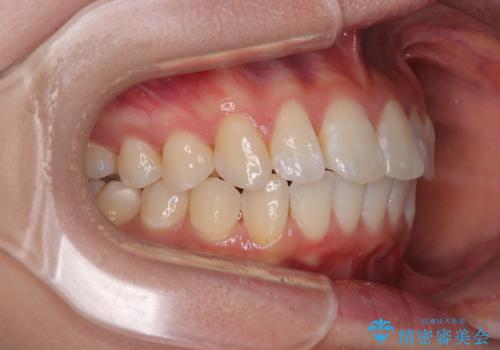

深い咬み合わせによる隙間 インビザライン矯正でコンプレックスを改善

- 上の前歯の隙間を気にして来院された患者様です。

インビザラインにより、上下の歯列を側方に拡大しつつ、前歯の隙間を閉じていくこととしました。

隙間の原因は強い咬合力や舌の突出癖、小帯の異常付着などがありますが、舌のトレーニングをしっかりと行いながら、装着時間を遵守して装着していただいたおかげで、スムーズに治療を終えることができました。